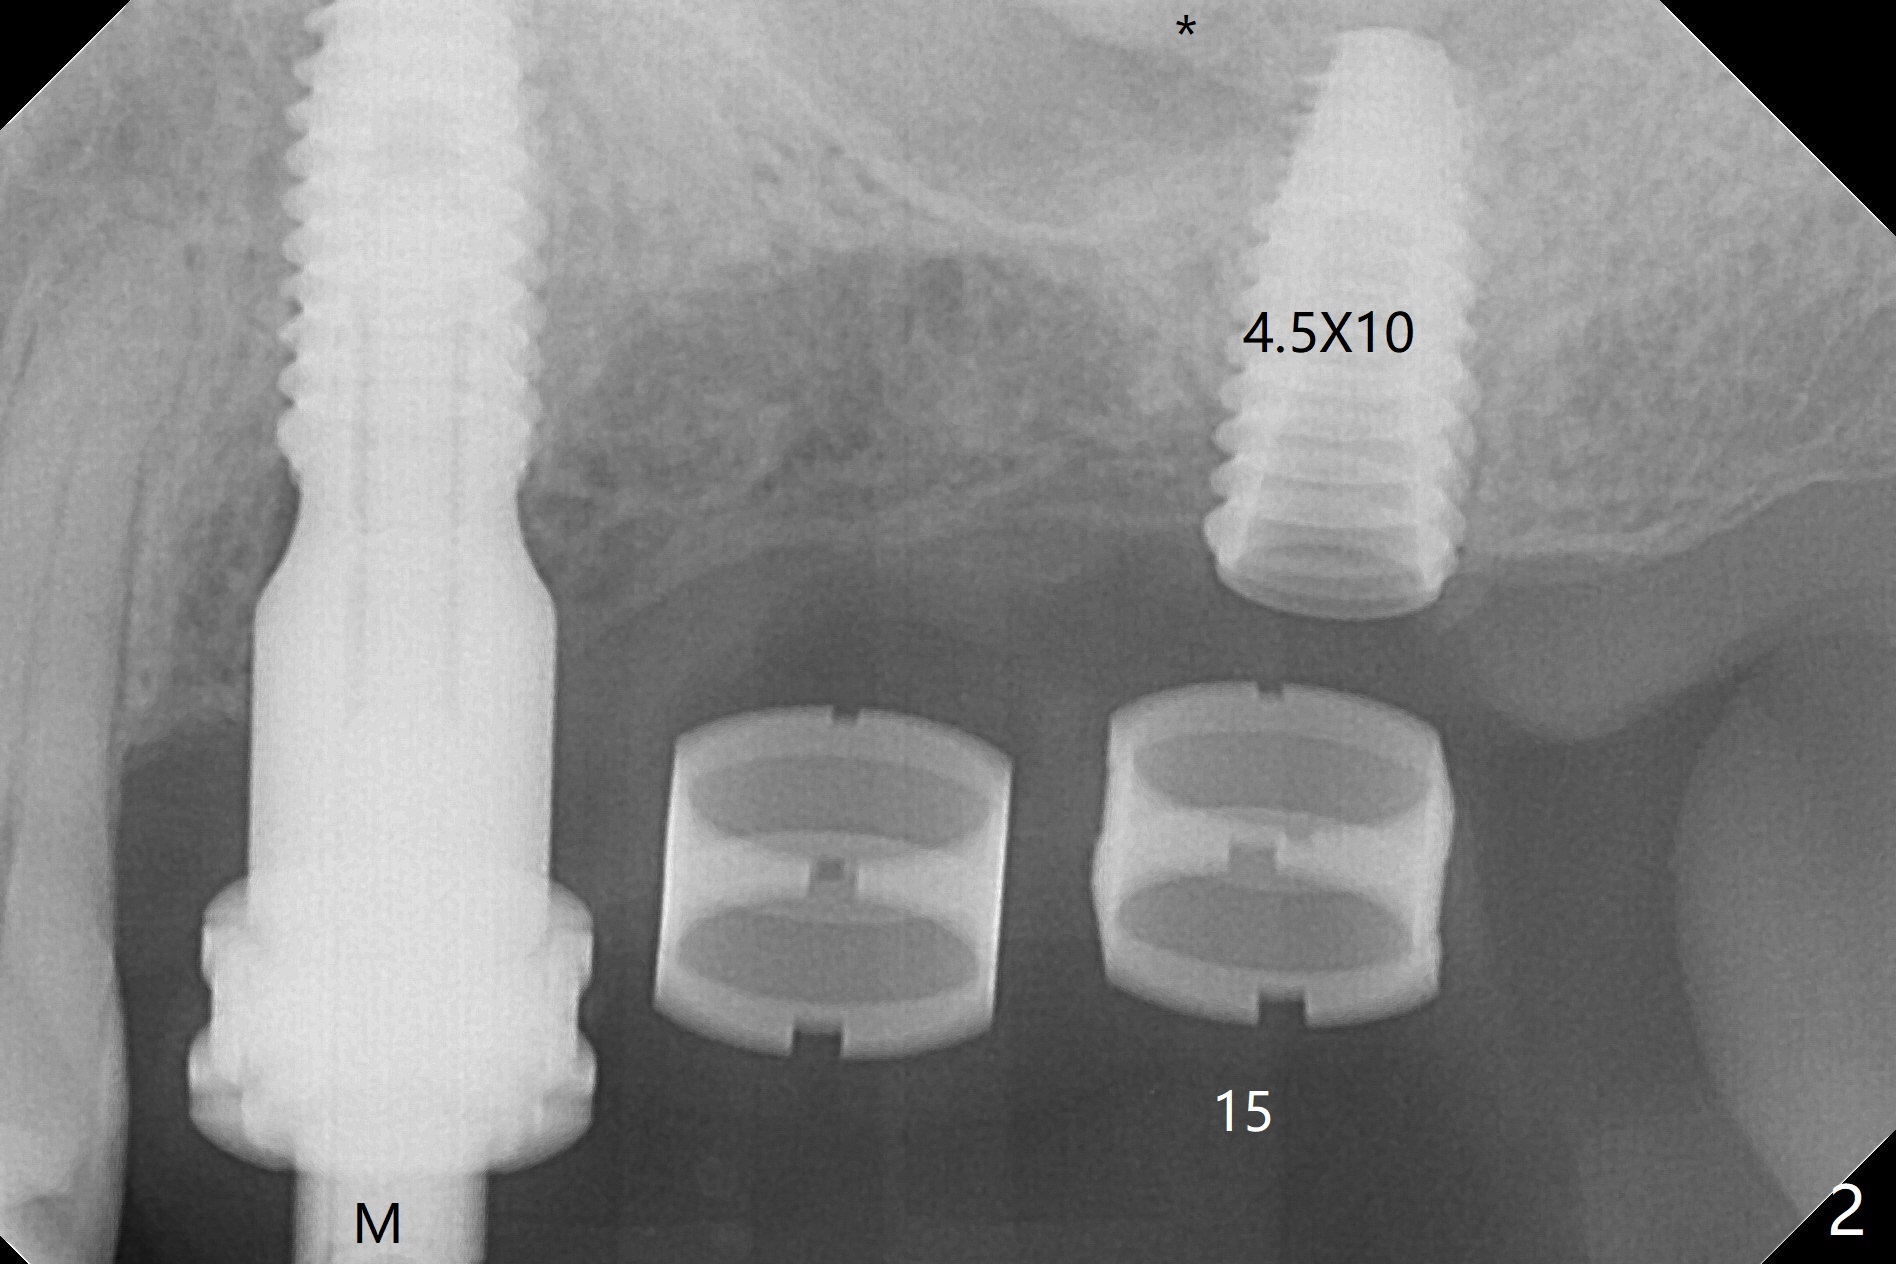

Extraction of abutment teeth associated with the loose FPD is not as easy as expected. Bony anchor placed at #14 (Fig.1 B) becomes loose while initial osteotomy a 2.2 mm drill at #13 for trajectory confirmation. The sinus membrane perforates at #15 when the sinus probe is being used. Luckily the perforation appears to be repaired with 2 pieces of PRF; sinus lift is assisted with a 4.5x10 mm dummy implant (Fig.2 *). Sinus lift at #14 is difficult and incomplete because of small osteotomy (Fig.3,5). In fact there is no sinus infection postop. Splinted immediate provisional is fabricated, but should be sectioned for individual units to form gingival scallops with distinct papillae. Three months postop, the splinted provisional is removed. The abutment at #14 is supragingival and is changed to 4.5x7(3) mm one. Individual temporary crowns are fabricated. Two weeks later, a small papilla forms between #14 and 15, while the temp at #13 is lost. The abutment at #13 changes to 4.5x7(5) mm one (Fig.7) with a new provisional, whereas those at #14 and 15 relined. In fact the abutment at #15 is incompletely seated (<) probably related to contact with the mesial crest (*). An abutment with smaller diameter and longer cuff at #15 seems to be completely seated (Fig.8,9, as compared to Fig.7). Following screw torque at 30 Ncm, impression is taken.